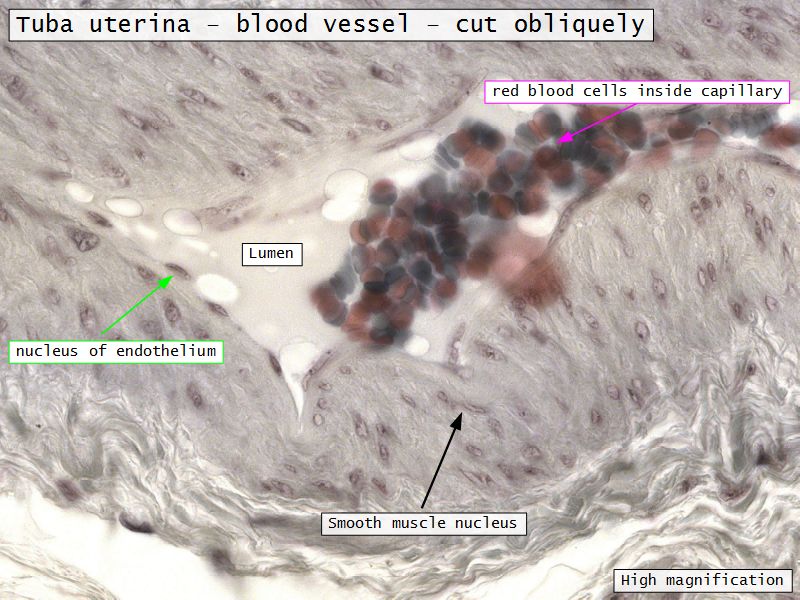

Tuba uterina

Tuba uterina

- Muscular tube

- Most frequent site of fertilization

- Conveys zygote to uterus

- Four regions

- Three layers

Three layers

- Mucosa

- Muscular layer

- Serosa

Muscular layer

- Ill-defined

- Inner circular

- Outer longitudinal

- Play role in moving zygote towards uterus

Serosa

- Simple squamous epithelium

- Contains

- Blood vessels

- Lymphatics

- Nerves